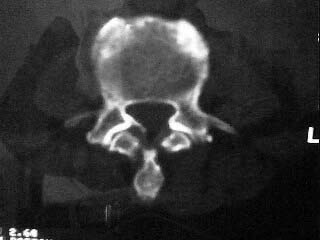

f,64。腰痛,腿麻三个月

是黄韧带钙化吗

腰椎退行性变;黄韧带钙化。

黄韧带增厚钙化